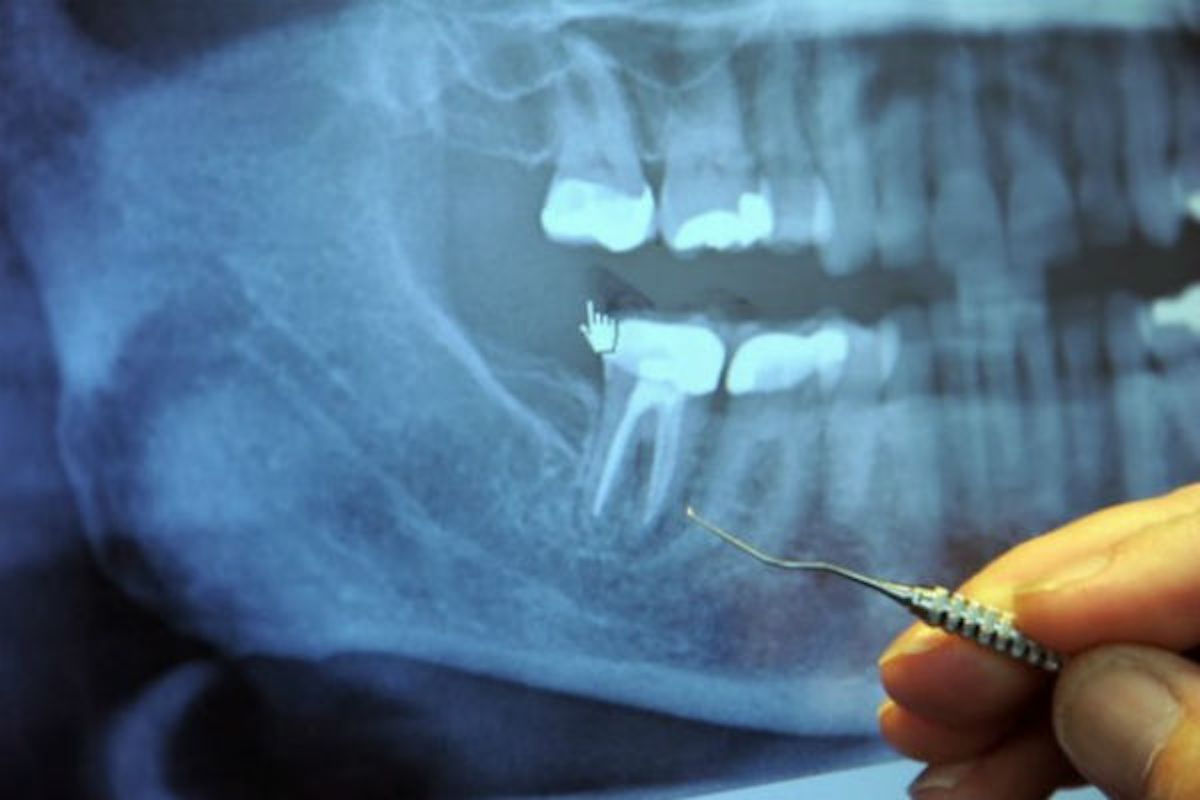

U pitanju je vađenje živca. Na milione ovih operacija se sprovede svake godine.

Kad zubar izvede operaciju vađenja živaca, on probuši zub, a zatim ispuni šupljinu supstancom koja odsijeca dotok krvi do zuba, tako da ona više ne može da cirkuliše kroz zub. Međutim, lavirint cijevčica i dalje ostaje tamo, a bakterije, koje više nemaju svoj izvor hrane, kriju se u ovim tunelima gdje su bezbjedne od antibiotika i imune odbrane organizma.

Korijeni svakog zuba dopiru do vilice i ostaju na svom mjestu zahvaljujući peridontalnom ligamentu. Stomatologe u školi uče da svaki zub ima 1-4 veća kanala. Međutim, postoji gomila kanala koja se uopšte ne pominje.

Svaki zub ima čitav lavirint sitnih cjevčica koje bi, kad bi se razmotale, bile dužine oko nekoliko kilometara. Veston Prajs je identifikovao 75 odvojenih pristupnih kanala u jednom centralnom sjekutiću.